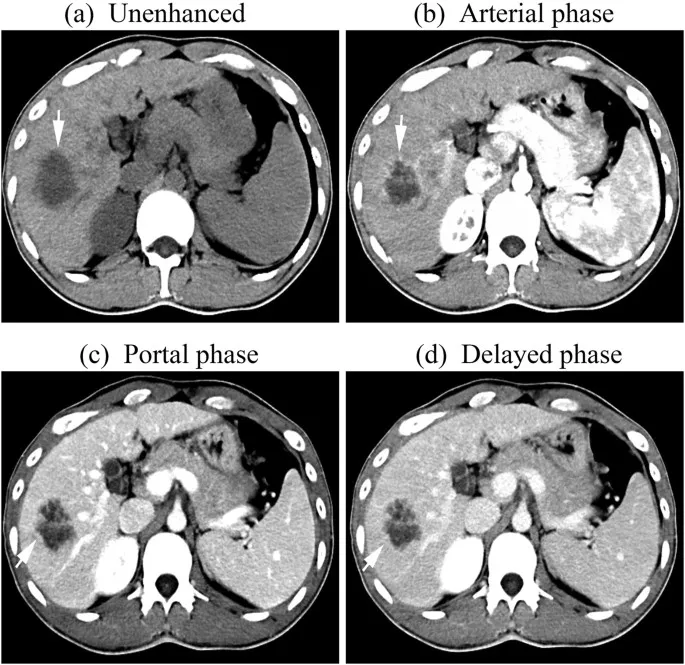

- Arterial Phase (~15-35s): Peak opacification of arteries and hypervascular structures.

- Late Arterial (~35-40s): Best for hypervascular tumors (e.g., HCC, renal cell carcinoma).

- Portal Venous Phase (~60-80s): Peak enhancement of portal veins and solid abdominal organs (liver, spleen, pancreas). The standard phase for most routine body scans.

- Delayed/Equilibrium Phase (>90s): Contrast washes out from normal tissues but is retained in fibrotic or scar tissue (e.g., cholangiocarcinoma) or washes out from lipid-rich tumors (adrenal adenoma).

⭐ HCC Washout: Hepatocellular carcinoma (HCC) classically shows intense arterial phase hyperenhancement (APHE) followed by rapid portal venous or delayed phase "washout," appearing hypodense compared to the liver.

- Arterial Phase: Best for hypervascular lesions (e.g., HCC, FNH).

- Portal Venous Phase (~70s): Peak uniform parenchymal enhancement; most metastases appear hypodense.